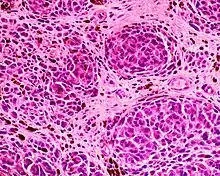

- Squamous cell carcinoma